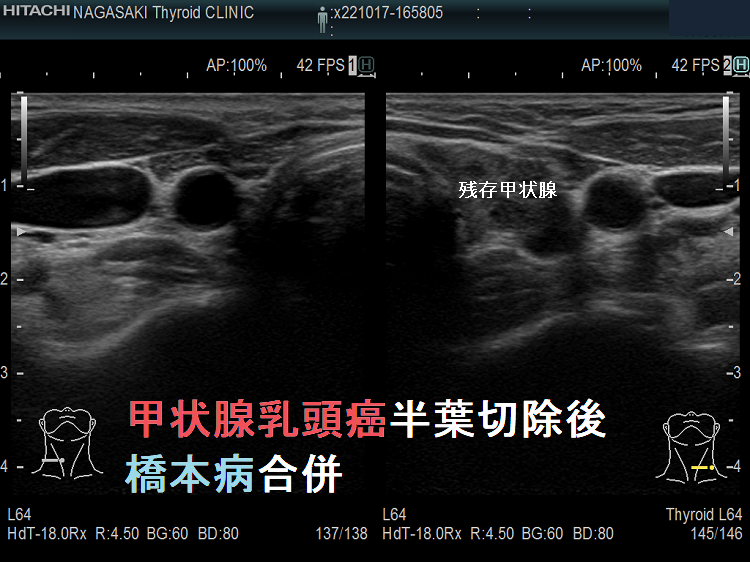

甲状腺乳頭癌半葉切除後 橋本病合併

甲状腺乳頭癌半葉切除後。残存甲状腺を見て分かるように、橋本病の破壊性変化が強く、抗サイログロブリン抗体(Tg-Ab)陽性です。

ただし、甲状腺全摘出と異なり半葉切除では、正常な甲状腺濾胞細胞が残っているため、サイログロブリンを産生するのは甲状腺分化癌(乳頭癌濾胞癌)だけではありません。そのため、代理的腫瘍マーカーとしての抗サイログロブリン抗体(Tg-Ab)の信頼性は低くなります。